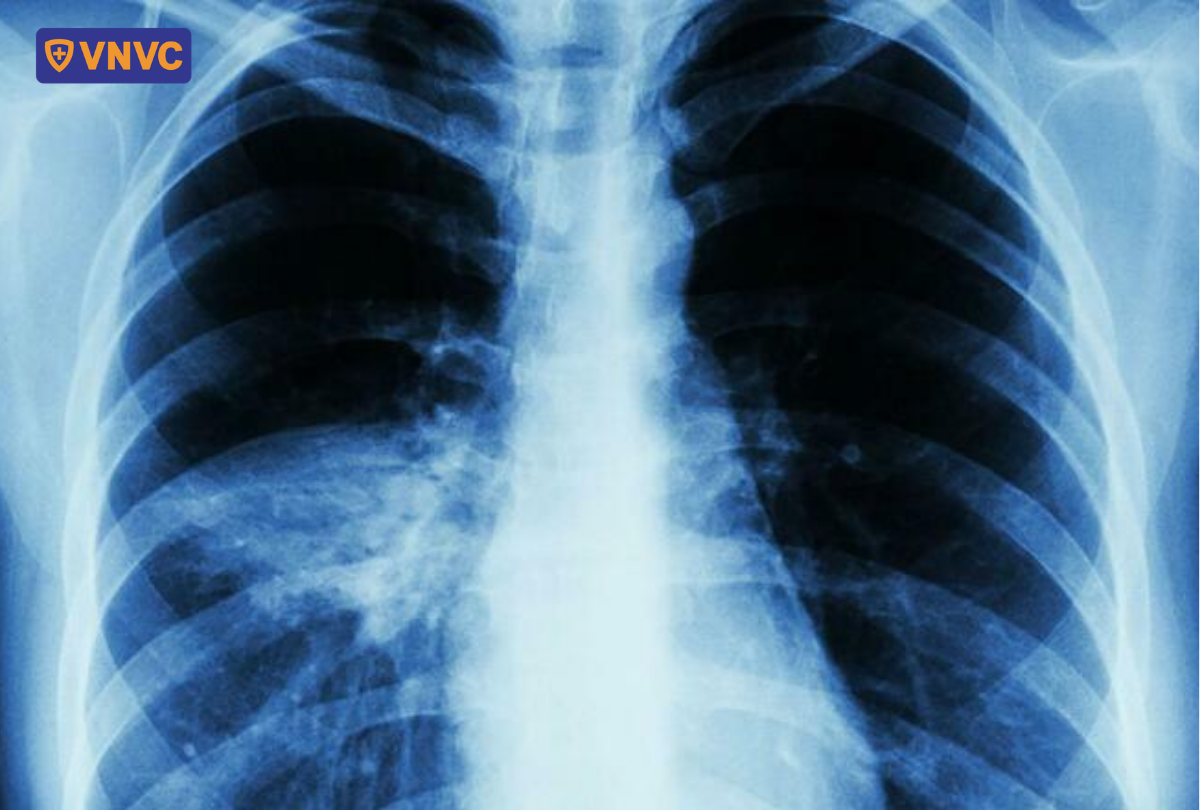

- Viêm phổi: Biến chứng này thường xuất hiện ở người lớn vào ngày thứ 3 đến thứ 5 của bệnh, dẫn đến suy hô hấp, phù phổi và gây nguy hiểm đến tính mạng.